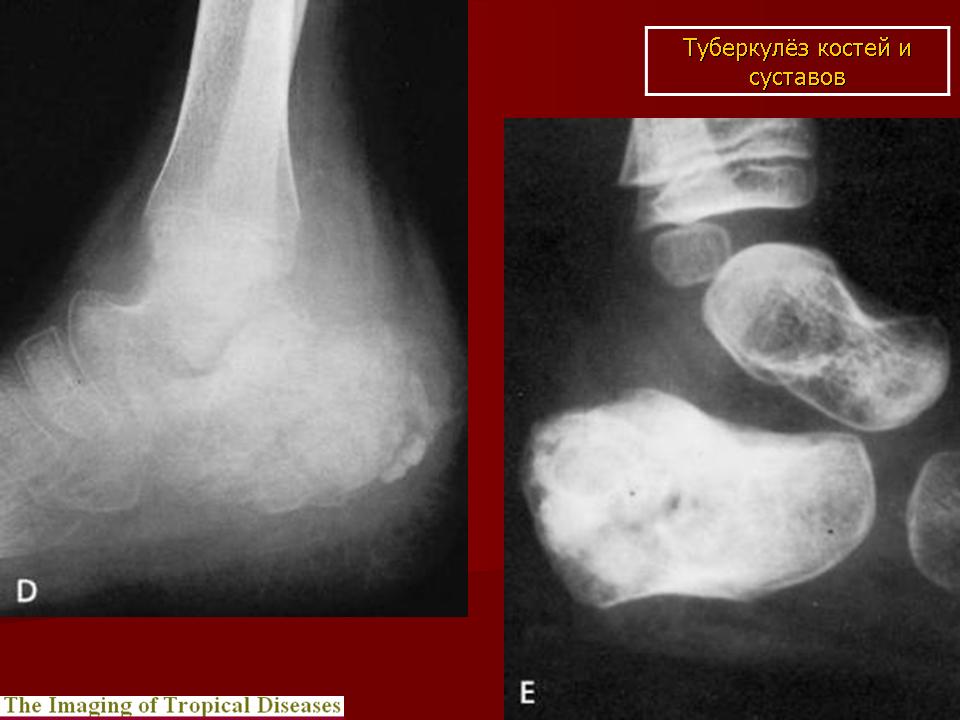

Медицинские аспекты заболеваний: рентгенологическая картина туберкулеза костей

Раздел: Снимки-откровения